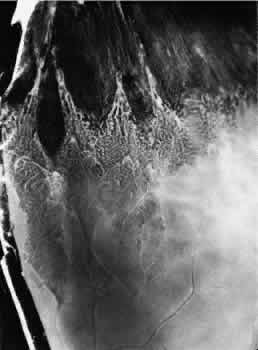

The anterior edge of the peripheral retina is theora serrata, an irregularly scalloped border; the irregularities are more pronounced nasally than temporally and have extreme individual variations in contour (Fig. 5). Dentate or toothlike processes extend anteriorly from the main contour of this bor-der, and bays or indentations extend posteriorly from the main contour of the ora serrata. At theora serrata, those projections of the retina toward the vitreous body are termed meridional folds. There is a concentration of dentate processes, ora bays, and meridional folds in the superior nasal quadrant and a progressive decrease in these morphologic features in the inferior nasal, superior temporal, and inferior temporal quadrants (Figs. 6 and 7). Although individual variations in ora serrata contour may be extreme, studies of adult human eyes demonstrate that both of a patient's eyes are remarkably similar and that statistically, the “average” ora serrata has 16 dentate processes, 1 large or giant dentate process, 10 ora bays, and 1 double ora bay.1,2

Fig. 5. Composite scale drawing depicts peripheral retina, ora serrata, ciliary body, and lens as viewed from posterior aspect. Ora serrata have more dentate processes and ora bays in the nasal quadrants than in the temporal quadrants.

Fig. 6. Peripheral fundus showing preequatorial retina, ora serrata, and inner surface of ciliary body (smooth portion, pars plana; portion with ciliary processes, pars plicata). Ora serrata in this nasal sector shows largely short dentate processes that are typical; that is, they align with valleys between ciliary processes. On right, a giant dentate process is atypical; that is, it aligns with a ciliary process. Aligned with and posterior to the atypical dentate process is a focus of retinal thinning (peripheral retinal excavation). (× 14.)